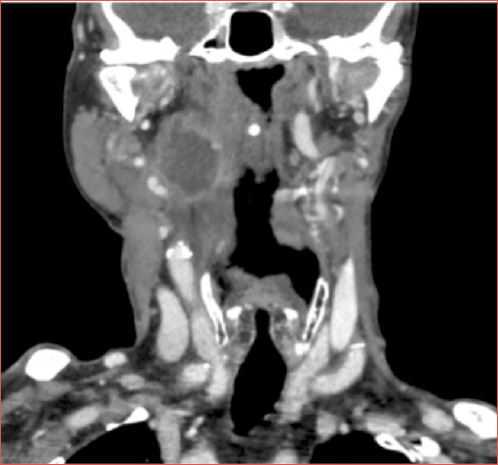

Objective: Parapharyngeal space (PPS) is a rare and unusual site of head and neck squamous cell carcinoma (SCC) metastases. Treatment strategy for PPS metastases is still not well defined. This research aims to investigate the clinical implications and oncological outcomes of SCC metastases in PPS.

Results: The retrospective chart review showed that the oropharynx was the most frequent primary tumour site. The advanced stage at the time of diagnosis was related to poorer survival and higher recurrence rates. A significant difference in 2-year overall survival in the subgroup of patients who experienced PPS metastases within the primary treatment and those who experienced PPS metastases as regional recurrence (66.7 vs 30.8%) was observed. Similar low survival rates were reported in the literature review with a mean overall and disease-free survival of 19.8 and 8.6 months, respectively.

Conclusions: PPS metastases are associated with a dismal prognosis, especially when diagnosed as regional recurrence after primary treatment, due to patients' poor general conditions and difficulty of treatment.